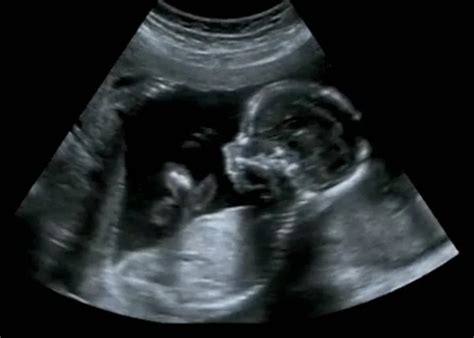

A magzati ultrahang szerepe a fejlődési rendellenességek felismerésében

A magzati ultrahang az egyik legfontosabb szűrővizsgálat a várandósság alatt, mivel lehetőséget ad a fejlődési rendellenességek időben történő felismerésére. Az ultrahangvizsgálatok során a szakemberek ellenőrzik a magzat méretét, szerveinek fejlődését, a méhlepény működését és a magzatvíz mennyiségét. A cél, hogy időben felismerjék azokat a kóros eltéréseket, amelyek befolyásolhatják a baba életkilátásait vagy a szülés módját.

Bizonyos rendellenességek már a 12-14. heti ultrahangon is láthatók, míg másokat csak a 18-22. heti genetikai vizsgálaton lehet pontosabban megállapítani. Genetikai eltérések (pl. Down-szindróma - nyaki redőmérés, orrcsont vizsgálata), szívfejlődési rendellenességek (veleszületett szívhibák), idegrendszeri eltérések (pl. nyitott gerinc, agyfejlődési problémák), végtag- és csontfejlődési problémák, hasfal- és rekeszizomsérvek, veseeltérések szűrhetők ki időben.

Bár az ultrahang segíthet genetikai betegségekre utaló jelek felismerésében, önmagában nem ad 100%-os diagnózist. Ha eltérés gyanúja merül fel, az orvos kiegészítő vizsgálatokat (pl. kombinált teszt, magzati DNS-teszt, amniocentézis) javasolhat a pontosabb eredmény érdekében.

A magzati ultrahang nem használ sugárzást, és nincs bizonyított káros hatása. Orvosi indokkal akár többször is biztonságosan elvégezhető.